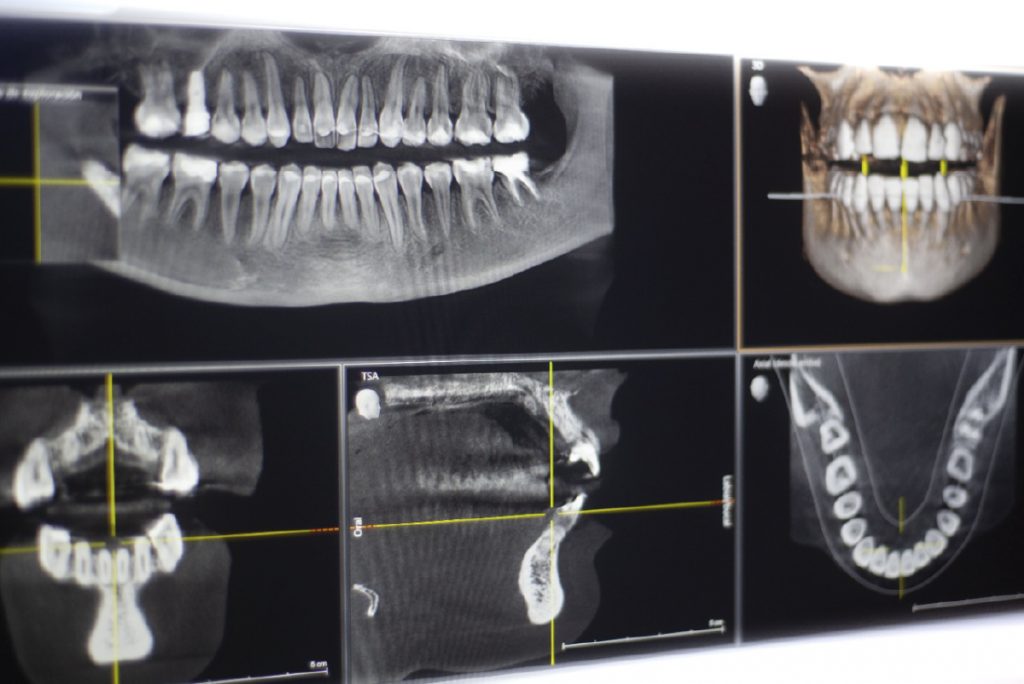

Nuestro Sanatorio cuenta en ambas sedes con ortopantomógrafos Cone Beam de última generación para realizar imágenes panorámicas dentales y tomografías 3D utilizadas en el diagnóstico odontológico.

La ortopantomografía es uno de los estudios más frecuentes y solicitados en odontología, ya que permite obtener imágenes panorámicas dentales de alta resolución y calidad, siendo de gran utilidad en el diagnóstico odontológico.

Este equipamiento de última generación cuenta con un sistema denominado Cone Beam, el cual permite realizar tomografías 3D de ambos maxilares y de las articulaciones temporomandibulares.

A diferencia de otros métodos, este software brinda una mayor resolución espacial gracias a sus altas matrices de reconstrucción y, por lo tanto, una reproducción tridimensional con detalle anatómico optimizado.

La tomografía 3D es utilizada, principalmente, en casos de implantes dentales que revisten cierta dificultad o en tratamientos quirúrgicos complejos.

Para el profesional de la odontología es una importante herramienta que le permite analizar en profundidad las estructuras óseas, nerviosas y dentales, brindándole información valiosa en múltiples planos.